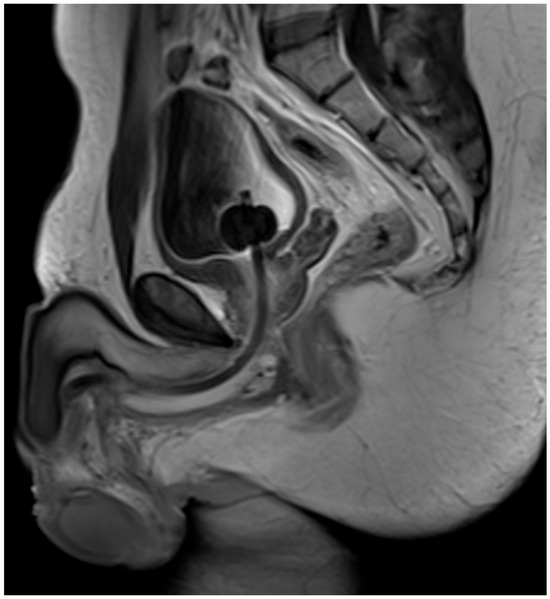

The Presentation and Treatment of Myointimoma: A Systematic Review and the First Case Report of Penile Myointimoma as a Cause of Urethral Obstruction

by Deirdre Maria König-Castillo, Armin Henning, Richard Wasicky, Clemens Kinsky, H. Christoph Klingler and Eva M. Compérat

Background/Objectives: Myointimoma is a rare, benign soft tissue tumor of the penis. We present a systematic review of the current literature and a case report of a 33-year-old male with a urethral stricture without discernible risk factors. Our aim was to investigate current [...] Read more.

Background/Objectives: Myointimoma is a rare, benign soft tissue tumor of the penis. We present a systematic review of the current literature and a case report of a 33-year-old male with a urethral stricture without discernible risk factors. Our aim was to investigate current knowledge on Myointimomas and increase the awareness of this entity. Methods: A systematic literature search was conducted across EMBASE, MEDLINE, PubMed, Scopus, Web of Science, and Google Scholar. Only 30 previously reported cases of this tumor are known—all located at the glans penis or in close proximity to it. Results: After the exclusion of non-eligible studies, 14 studies were included. Conclusions: Myointimomas are a relevant differential diagnosis in recurring cases of bladder outlet obstruction. Full article